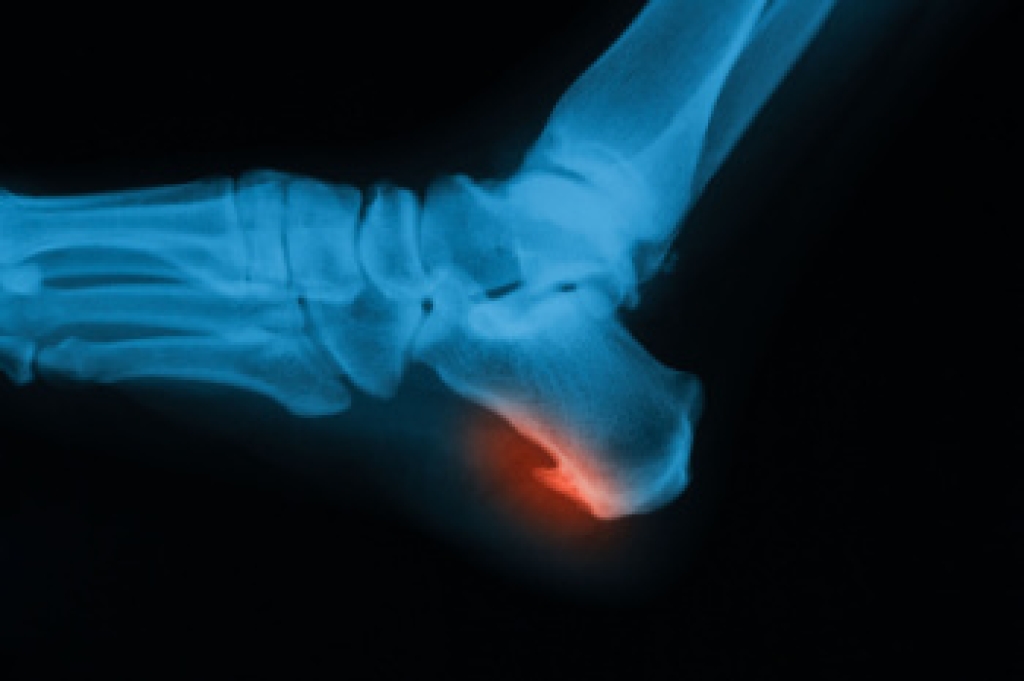

Congenital foot problems are deformities affecting the feet, toes, and/or ankles that children are born with. Some of these conditions have a genetic cause while others just happen. Some specific foot ailments that children may be born with include clubfeet, polydactyly/macrodactyly, and cleft foot. There are several other foot anomalies that can occur congenitally. What all of these conditions have in common is that a child may experience difficulty walking or performing everyday activities, as well as trouble finding footwear that fits their foot deformity. Some of these conditions are more serious than others. Consulting with a podiatrist as early as possible will help in properly diagnosing a child’s foot condition while getting the necessary treatment underway.

- Vertical talus, where the talus bone forms in the wrong position causing other bones in the foot to line up improperly, the front of the foot to point up, and the bottom of the foot to stiffen, with no arch, and to curve out.